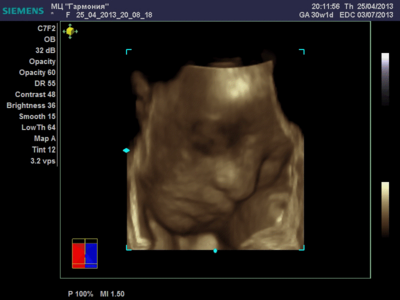

Еще одна Джианнка:

| Вложения: |

KENZEL,OLESYA_5.JPG [ 60.02 КБ | Просмотров: 1513 ]